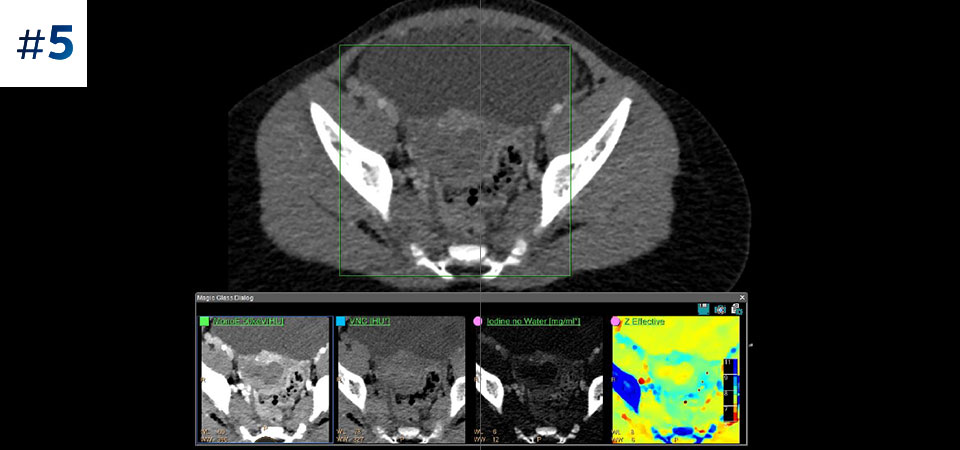

Reviewing spectral images

Go beyond conventional CT. See how layers of spectral-detector results can enhance your diagnostic confidence.

Abdomen pelvis